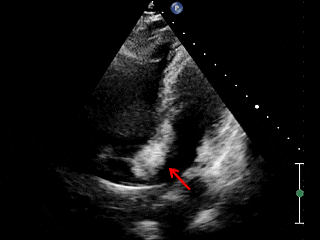

释放后超声

四腔心切面